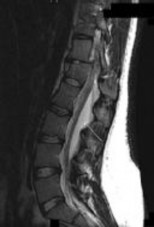

Figures 1 through 3 show sagittal and axial MRIs and a radiograph from a

77-year-old woman with leg pain when standing and walking of 1 year duration. The pain improves when she leans forward. She has been in physical therapy, taken oral analgesics, and had epidural injections with minimal relief. What is the best next step?

The patient has lumbar stenosis of L2-3 and L3-4. She has no spondylolisthesis or instability. For her condition, spinal fusion plays a minimal role. She has no evidence of instability, and her condition can be addressed through laminectomy only. No role exists for microdiskectomy, because her disease results from a combination of ligamentum flavum hypertrophy and facet hypertrophy.